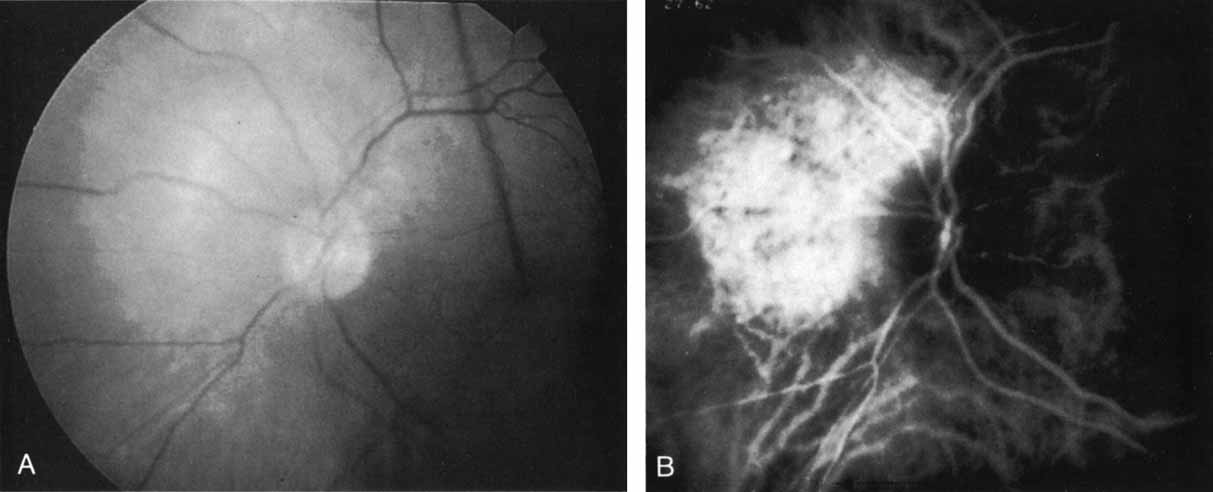

ICG angiography in amelanotic melanomas reveals variable blockage, depending on the amount of pigmentation present in the lesion. Corkscrew vessels have been identified with ICG angiography, but not with fluorescein angiography, in some patients with amelanotic melanoma80,81 (Fig. 24). The meaning of this vascular pattern currently is unclear, but it may eventually assist in the differentiation of these primary ocular tumors from metastatic lesions.

Fig. 24 A. Clinical photograph of a patient with an amelanotic melanoma adjacent to the optic nerve head. B. Mid-phase indocyanine green angiogram demonstrating corkscrew vessels within the melanoma.

CHOROIDAL HEMANGIOMA

ICG angiography definitely provides a clearer delineation of nonpigmented vascular choroidal tumors than does fluorescein angiography. With choroidal hemangioma, marked progressive hyperfluorescence with intense late staining and leakage is seen on the ICG study82 because of the high vascularity of the lesion.80,81,83,84 (Fig. 25). A speckled pattern within the lesion as well as stellate borders have been noted in some patients.80,81,83 Better visualization of the lesions can be achieved as a result of improved imaging through the serosanguineous retinal elevations typically accompanying the hemangiomas.

Fig. 25 A. Clinical photograph of a patient with a choroidal hemangioma adjacent to the optic nerve. (Courtesy of Dr. Carol Shields.) B. Mid-phase indocyanine green angiogram demonstrating hyperfluorescence and staining of the hemangioma, which has well-defined margins. (Courtesy of Dr. Carol Shields.)